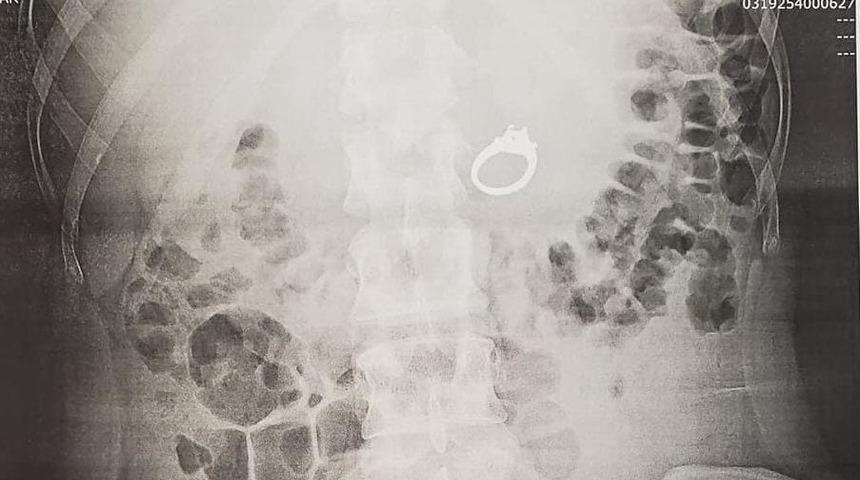

Röntgen çekildiğinde ise yaşananların rüya değil gerçek olduğu ortaya çıktı. Zira yüzük genç kadının midesindeydi.

29 yaşındaki kadın, doktorlara olayın sebebini anlattı. Uzmanlar ise kadına bir uyku terapistiyle görüşmesini tavsiye etti. Ancak şimdi çok daha büyük bir sorunla karşı karşıyaydı. Yuttuğu yüzük midesinden nasıl çıkarılacaktı?